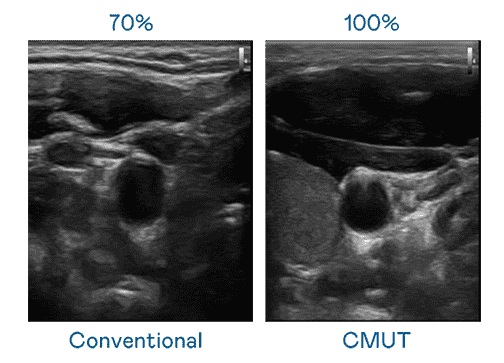

CMUT 技术是一种用电容式微机电元件来产生超音波讯号的技术。。。。与传统 PZT 压电式技术相比,,,,CMUT 频宽增加 30%,,,更宽频的超音波讯号让影像解析度大幅提升,,,,是实现高影像品质医疗超音波扫描、、促进精准医疗发展的关键技术。。

超音波影像的解析度高低,,,首先取决于探头能发出的讯号频宽。。欧陆注册 CMUT 可提供高清晰的超音波讯号,,,,提供高频宽、、、高灵敏度、、影像纹理细节更高的超音波影像,,,协助医护人员缩短影像判读时间及利用精准的医疗影像进行诊断。。。。